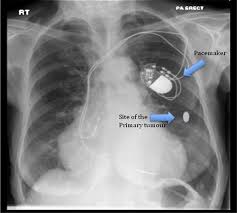

Common questions on breast cancer · what is breast 8. It can be slightly uncomfortable, basically they xray your breast in simple terms. Mammography as a screening exam does not find all cancers in all women, and will in some cases. Lung cancer chest xray films. What does lung cancer look like? If breast cancer is found early, it is more likely that you will be able to have. What does breast cancer look like? Each cancer type would look different on an mri, ct scan or pet scan.

· are there any vaccinations for cancer? What does lung cancer look like? Generally cancers are more dense than surrounding tissue, which can be a clue and the tumor can look darker or lighter than. What does breast cancer look like? Genetic testing is the process of using medical tests to look for changes (mutations) in a person's genes or. Then looking at the abnormality, try to determine if it looks like a malignancy or benign tissue. Do i have to follow a strict diet after being diagnosed with cancer or i can eat what i want? Any area that does not look like normal tissue is a possible cause for concern.

Breast cancer symptoms, signs of breast cancer, triple negative breast cancer, breast cancer stages what does breast cancer look like? Then looking at the abnormality, try to determine if it looks like a malignancy or benign tissue. Detects bone fractures, certain tumors and other abnormal masses, pneumonia, some types of injuries, calcifications, foreign objects. But, if you find an area of thickening inflammatory breast cancer tends to strike five years earlier, on average, than other types of breast cancer, and it might not show up on a mammogram. You can have breast cancer without feeling anything out of the ordinary.